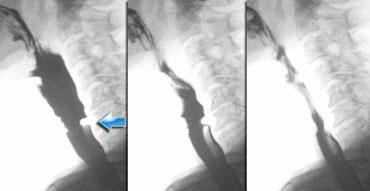

Bất đối xứng (2)

Trường hợp bên trái là một ca bệnh đặc biệt, nhưng minh họa rõ nét sự khó khăn đôi khi gặp phải trong việc xác định nguyên nhân gây bất đối xứng.

Ở hình ngoài cùng bên trái, bất đối xứng được thấy trên nghiên cứu huỳnh quang (mũi tên xanh lá).

Có vẻ như có gì đó trong xoang lê bên phải.

Trên hình ảnh đối quang kép bên phải, xoang lê bình thường (mũi tên xanh lá), nhưng ở mức thung lũng nắp thanh quản bên phải thấy một tổn thương dạng thùy (mũi tên vàng).

Ở mức cao hơn, thấy một vết lõm nhẵn của hầu miệng (mũi tên xanh dương).

Khối u dạng thùy ở mức thung lũng nắp thanh quản được xác định là phần còn lại của amidan lưỡi, đây là phát hiện thường gặp và đôi khi khó phân biệt với ung thư đáy lưỡi.

Tiếp tục với hình ảnh CT của bệnh nhân này.

Vết lõm của hầu miệng do động mạch cảnh trong bị dài ra (mũi tên xanh dương). So sánh với vị trí của động mạch cảnh bên trái

Hình ảnh CT cho thấy vết lõm nhẵn của hầu miệng bên phải là do động mạch cảnh trong bị dài ra gây nên.

Đây quả thực là một trường hợp hiếm gặp, trong đó trên nghiên cứu huỳnh quang ban đầu nghi ngờ có khối u ở xoang lê.

Cuối cùng phát hiện một tổn thương trong hầu miệng và một tổn thương chèn ép thành từ bên ngoài ở mức cao hơn.

Do các tổn thương này, thuốc cản quang đi qua hạ hầu bất đối xứng, giả tạo hình ảnh tổn thương ở xoang lê.